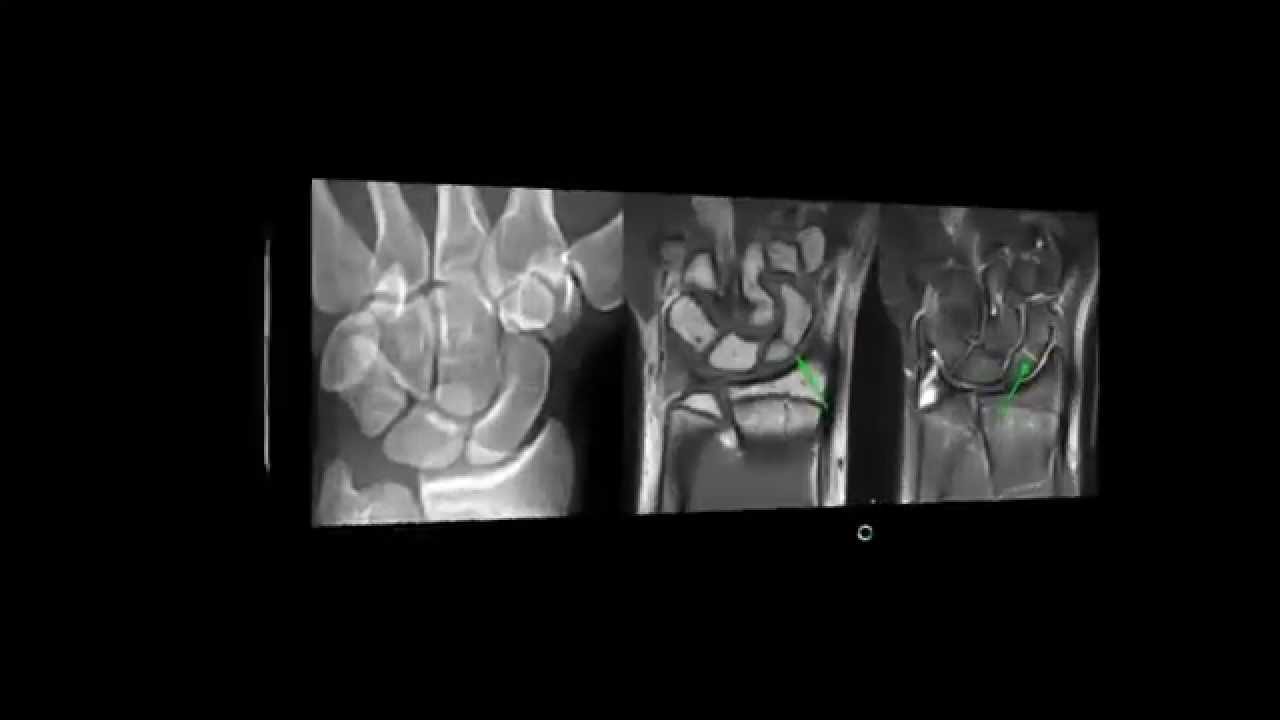

do olécrano Este um outro caso que é importante lembrar que às vezes quando você tem a lua do rádio é importante você radiografar o antebraço inteiro porque você pode ter luxação do rádio e fratura da una Então você fratura a una ele cavalga né ele encurta e o rádio luxa Então essa Associação é É frequente Então temos que tomar esse Cuidado se tem luxação aqui do rádio você tem que radiografar o o antebraço todo justamente para procurar aí a fratura da una Vamos a um outro caso aqui um caso o raio x tá bem feitinho